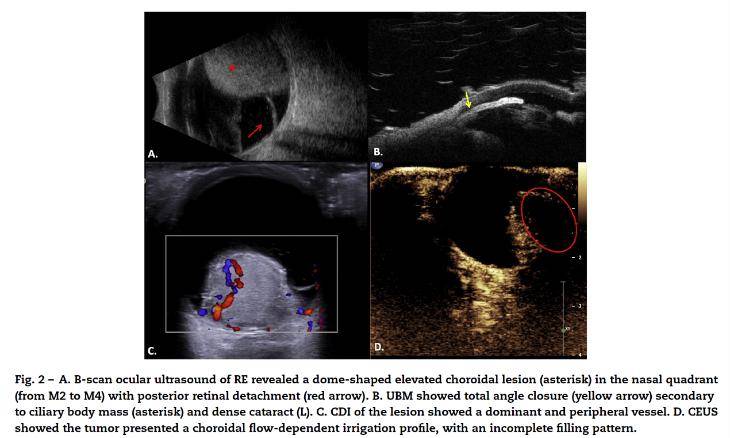

世界青光眼周丨深入探索青光眼患者的世界病例荟萃揭示诊疗之路一